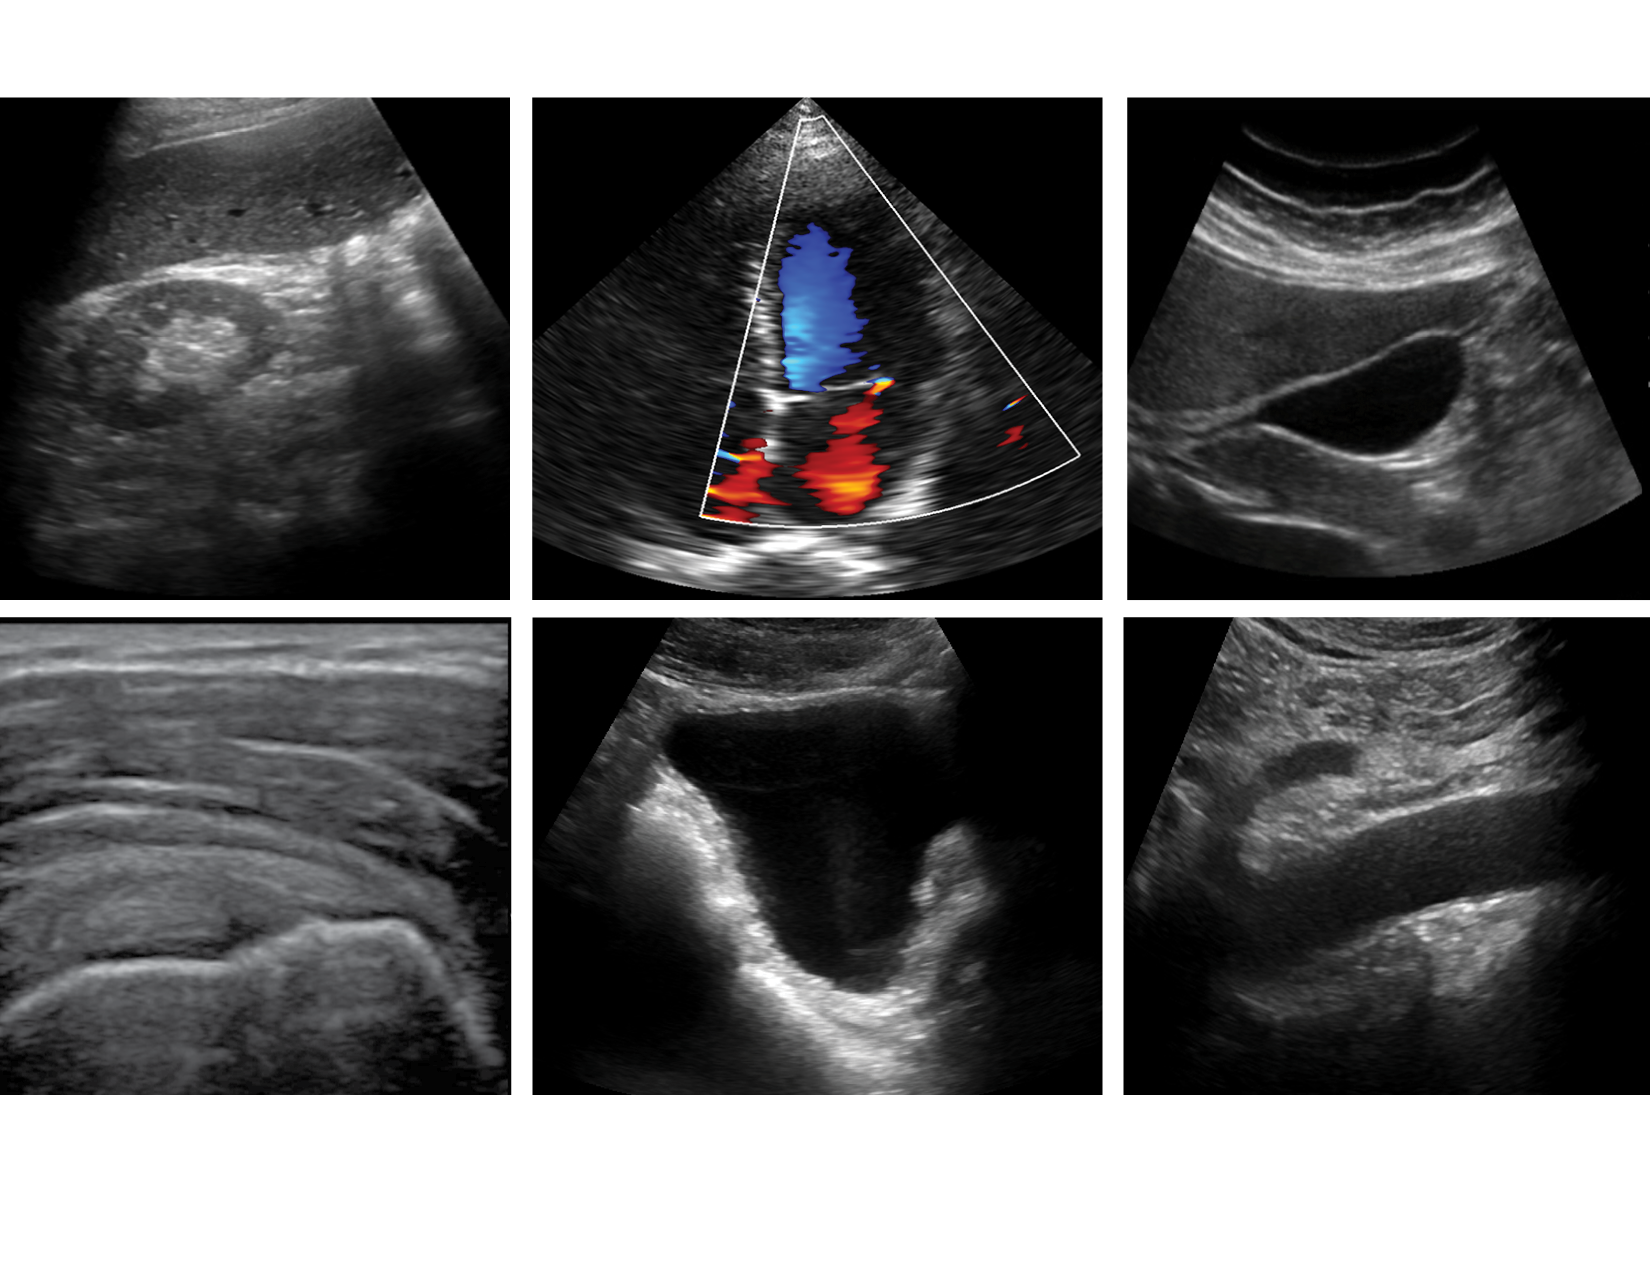

The use of POCUS, or point-of-care ultrasound, has substantially increased in recent years, and for good reason, given its accuracy in driving key answers to medical questions at the bedside. Handheld ultrasound or portable ultrasound technology allows medical professionals to provide safe and effective medical imaging to improve care. Recently, POCUS devices have become an essential aid in the diagnosis of COVID-19 and other pulmonary infections. Portable ultrasounds can be a more rapid method for obtaining diagnostic imaging for all patients.

It should be noted that portable ultrasound devices are not intended to replace traditional types of ultrasound systems. Like all medical technologies, POCUS is only accurate when applied to appropriate use cases. Portable ultrasound devices produce extremely accurate results when used to answer patient-focused questions. Handheld ultrasound systems allow the clinician to answer diagnostic questions and aid in the accuracy of performing procedures at the bedside.